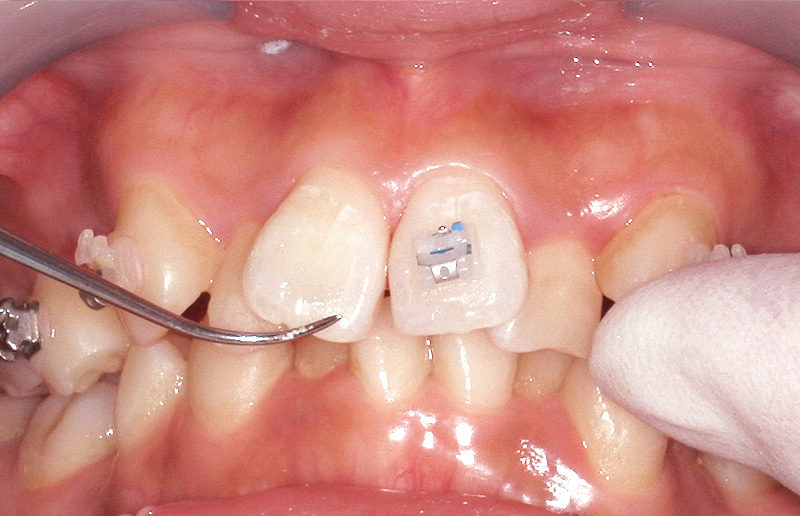

使用方法は「スーパーボンド」と同様であるが、「ボンドフィルSBⅡ」の特徴的な点は粉液比にあり、「キャタリストV」1滴に対し液材3滴の割合で使用する(図8)。被着体ごとの適切な前処理を行った後、筆積法を用いてブラケットを被着面に圧接し、はみ出した余剰レジンを除去する。次に光照射を行い、最低3分以上経過後に十分な重合を確認してからワイヤーを装着する(図9~12)。ただし、「スーパーボンド」および「ボンドフィルSBⅡ」は最終的な硬化が完了するまでに24時間を要するとされている。特にジルコニア冠やCAD/CAMレジン冠などはブラケット脱離が多いことが報告されているため、接着強さおよび重合率が最大になる24時間経過後にワイヤーを装着することで、ブラケット脱離のリスクを軽減できると考えている。

![[写真] 慎重にブラケットを歯のFAポイントに位置付ける](/academic/dentalmagazine/wp-content/uploads/sites/2/2025/11/195-13_photo09.jpg)

図9 慎重にブラケットを歯のFAポイントに位置付ける。 -

![[写真] 探針で位置を微調整後、圧接](/academic/dentalmagazine/wp-content/uploads/sites/2/2025/11/195-13_photo10.jpg)

図10 探針で位置を微調整後、圧接 -

![[写真] 探針で余剰レジンを除去](/academic/dentalmagazine/wp-content/uploads/sites/2/2025/11/195-13_photo11.jpg)

図11 探針で余剰レジンを除去 -

![[写真] 硬化完了](/academic/dentalmagazine/wp-content/uploads/sites/2/2025/11/195-13_photo12.jpg)

図12 光照射後3分で硬化完了